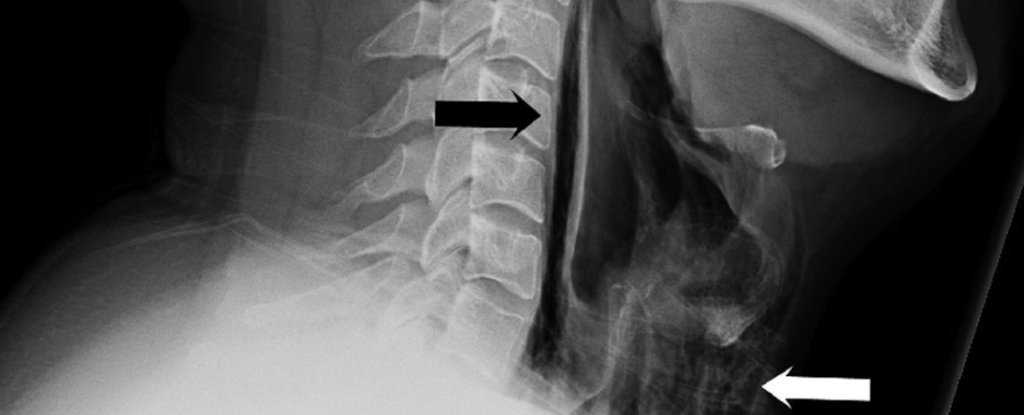

Симптомы начались после того, как мужчина сильно чихнул, несмотря на то, что старался сдержаться и для этого зажимал нос. Затем он начал жаловаться на острую боль, странный голос и припухлость шеи. Врачи обследовали мужчину, но не обнаружили никаких отклонений в легких и сделали рентгеновский снимок и компьютерную томографию. По снимкам стало ясно, что в шее и грудной клетке пациента имеется обширная эмфизема – скопление воздуха там, где его быть не должно. Диагноз гласил: спонтанный разрыв пищевода. После курса антибиотиков воспаление постепенно сошло на нет; во время лечения мужчина получал пищу через трубку, ведущую из носоглотки в желудок.